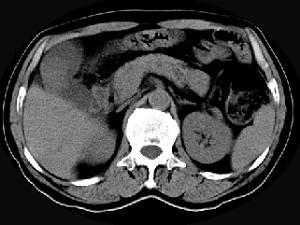

问题 男,45岁,右季肋区疼痛,Murphy征阳性,B超提示胆囊息肉,CT所见如图,最可能的诊断是 ( )

选项 A、胆囊转移癌 B、胆囊腺肌增生症 C、胆囊癌 D、慢性胆囊炎 E、胆囊息肉

答案 C